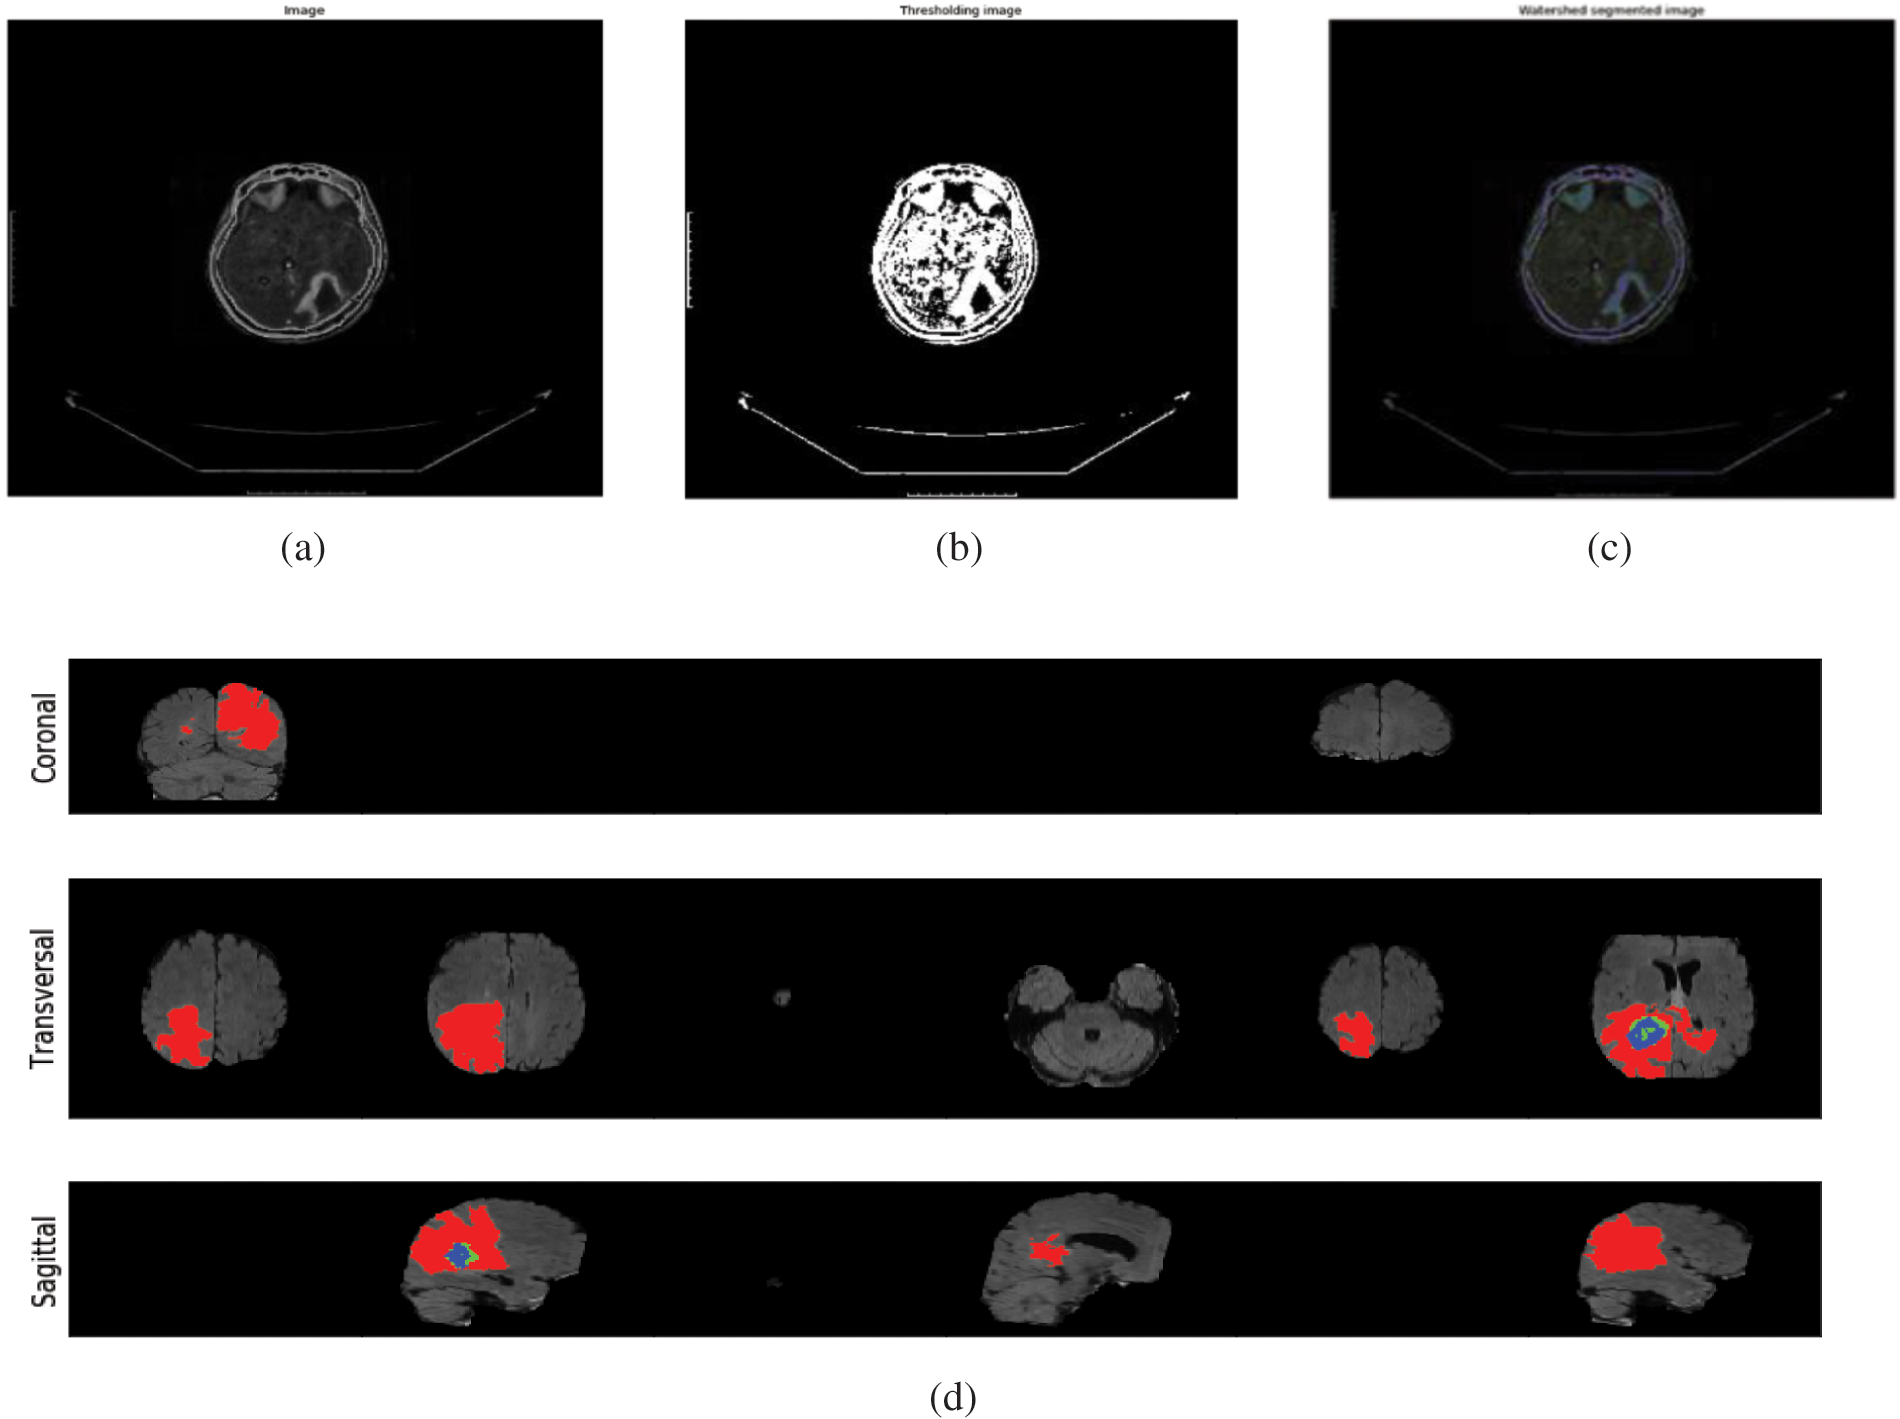

Fig. 4 outlines the melded pictures constituted by utilizing Picture Combination Calculations. This strategy aims to make images more worthy and comprehensible for human and machine perception, not fair to play down the sum of information. Multisensory picture combination could be a computer vision procedure that combines germane data from two or more pictures into a single image. On the other hand, Fig. 4d clarifies the segmenting of the infected region for the case of Sagitical, Transversal, and Coronal. The red mark indicates the regional segmentation towards automated measurements.

Figure 4: (a) Illustration of the normal images (b) demonstrating the thresholding Images (c) visualized the watershed segmented image (d) segmenting the infected region for the case of sagitical, transversal, and coronal. The red mark indicates the regional segmentation towards automated measurements